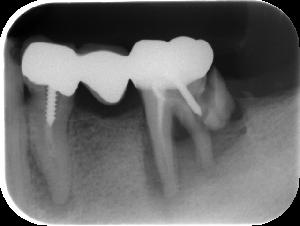

レントゲンのよる検査

表面からみただけではわからない歯や歯槽骨の状態を調べます。あごの状態も確認します。